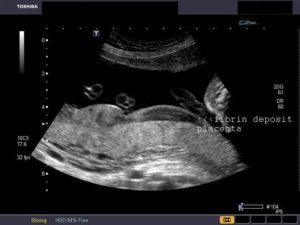

Важным этапом УЗИ обследования является диагностика патологий: кальцинатов, инфарктов, кист, опухолей и признаков отслойки плаценты.

Так, УЗИ-признаками кист являются эхонегативные жидкостные образования с четкими краями, а опухоли, при этом, имеют нечеткие границы. Инфаркты могут диагностироваться на УЗИ в виде очагов неправильной формы, с гиперэхогенными контурами.

Для дифференциации заболевания и установления точного диагноза применяется наиболее информационный метод инструментальной диагностики – ультразвуковое исследование.

Во время процедуры УЗИ изображение транслируется на экране монитора. Основным признаком кисты считается эхонегативное образование, имеющее чёткие контуры. У опухоли наблюдаются неровные размытые края.